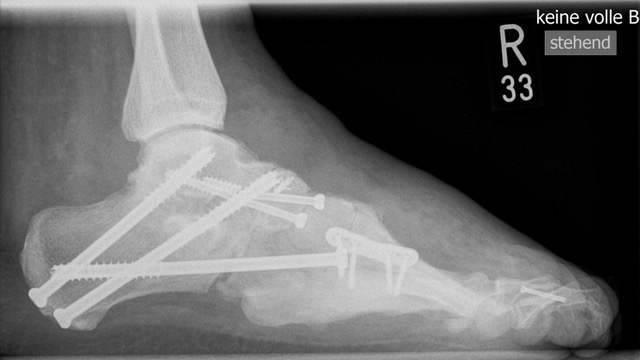

Elevierende schließende Basisosteotomie des proximalen Os metatarsale I oder plantar öffnende Osteotomie des Os cuneiforme mediale bzw. aller Ossa cuneifomia: Die pathologische Wirkung des plantarisierten Os metatarsale I wird durch Entnahme eines basisnahen dorsalen Keils neutralisiert (Abb. 26 und 27). Diese Operation wird immer mit einem zuvor durchgeführten plantaren Weichteilrelease kombiniert. Gelegentlich ist bei rigidem Rückfuß auch eine zusätzliche lateralisierende Calcaneusosteotomie erforderlich, um den Fuß plantigrad einzustellen (Abb.28)  32.

Calcaneusosteotomie nach Dwyer oder lateral verschiebende Calcaneusosteotomie: Besteht trotz Vorfußkorrektur noch eine Rigidität im Chopartgelenk bzw. im subtalaren Gelenk mit Varusdeformität des Calcaneus so ist eine lateral schliessende Keilosteotomie nach Dwyer oder eine valgisierende Verschiebeosteotomie des Calcaneus sinnvoll (Abb. 29), um den Fuß wieder orthograd unter die Tibiaachse zu stellen 28. Nachteil der Dwyer-Osteotomie ist die Verkürzung des Calcaneus. Bei der alternativen lateralen Verschiebung des Calcaneus sollte immer das Rentinakulum des Tarsaltunnels medialseitig geöffnet werden (Tarsaltdachspaltung), um einem Impingement mit neurovaskulären Komplikationen vorzubeugen.